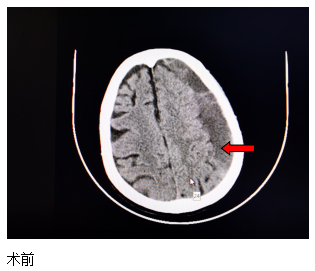

近日,一位84歲高齡患者來(lái)江寧中院就診,表現(xiàn)為:右側(cè)肢體的力量下降、不能獨(dú)立站立、言語(yǔ)不利、吐字不清。經(jīng)頭部CT檢查發(fā)現(xiàn),患者左側(cè)大面積慢性硬膜下血腫,嚴(yán)重壓迫腦組織。

患者收入院后,完善各項(xiàng)檢查,無(wú)明顯手術(shù)禁忌,中醫(yī)院神經(jīng)外科團(tuán)隊(duì)經(jīng)過(guò)精心周全的準(zhǔn)備,為其實(shí)施了腦膜中動(dòng)脈栓塞結(jié)合硬通道血腫穿刺引流的復(fù)合手術(shù)。術(shù)后第二天,患者肢體無(wú)力的癥狀得到了明顯改善,語(yǔ)言表達(dá)也恢復(fù)如初。患者及家屬對(duì)此治療效果非常滿意。